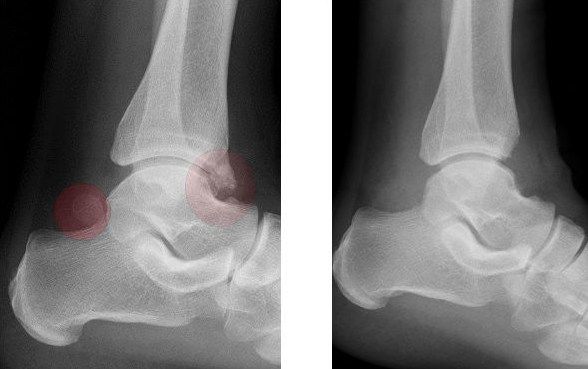

Röntgenbild eines Sprunggelenkes vor und nach Entfernung eines os trigonum und eines knöchernen Sporns (Osteophyt) - beides rot eingekreist

Im Bereich des unteren Sprunggelenks kann es zur Entwicklung eines zusätzlichen Knochenanteiles (os trigonum) kommen. Dies kann gerade im Zehenspitzenstand zu einer „Einklemmsituation" mit der Schienbeinkante führen. Zusätzlich kann es zu einer Mitreizung der Sehne des Großzehenbeugers kommen, was sich in einem ziehenden Schmerz, der sich häufig in die Fußsohle verlagert äußert. Besteht ein solches symptomatisches Os trigonum ist die Therapie der Wahl die operative Entfernung mittels arthroskopischer Technik, um das Weichteiltrauma möglichst gering zu halten.